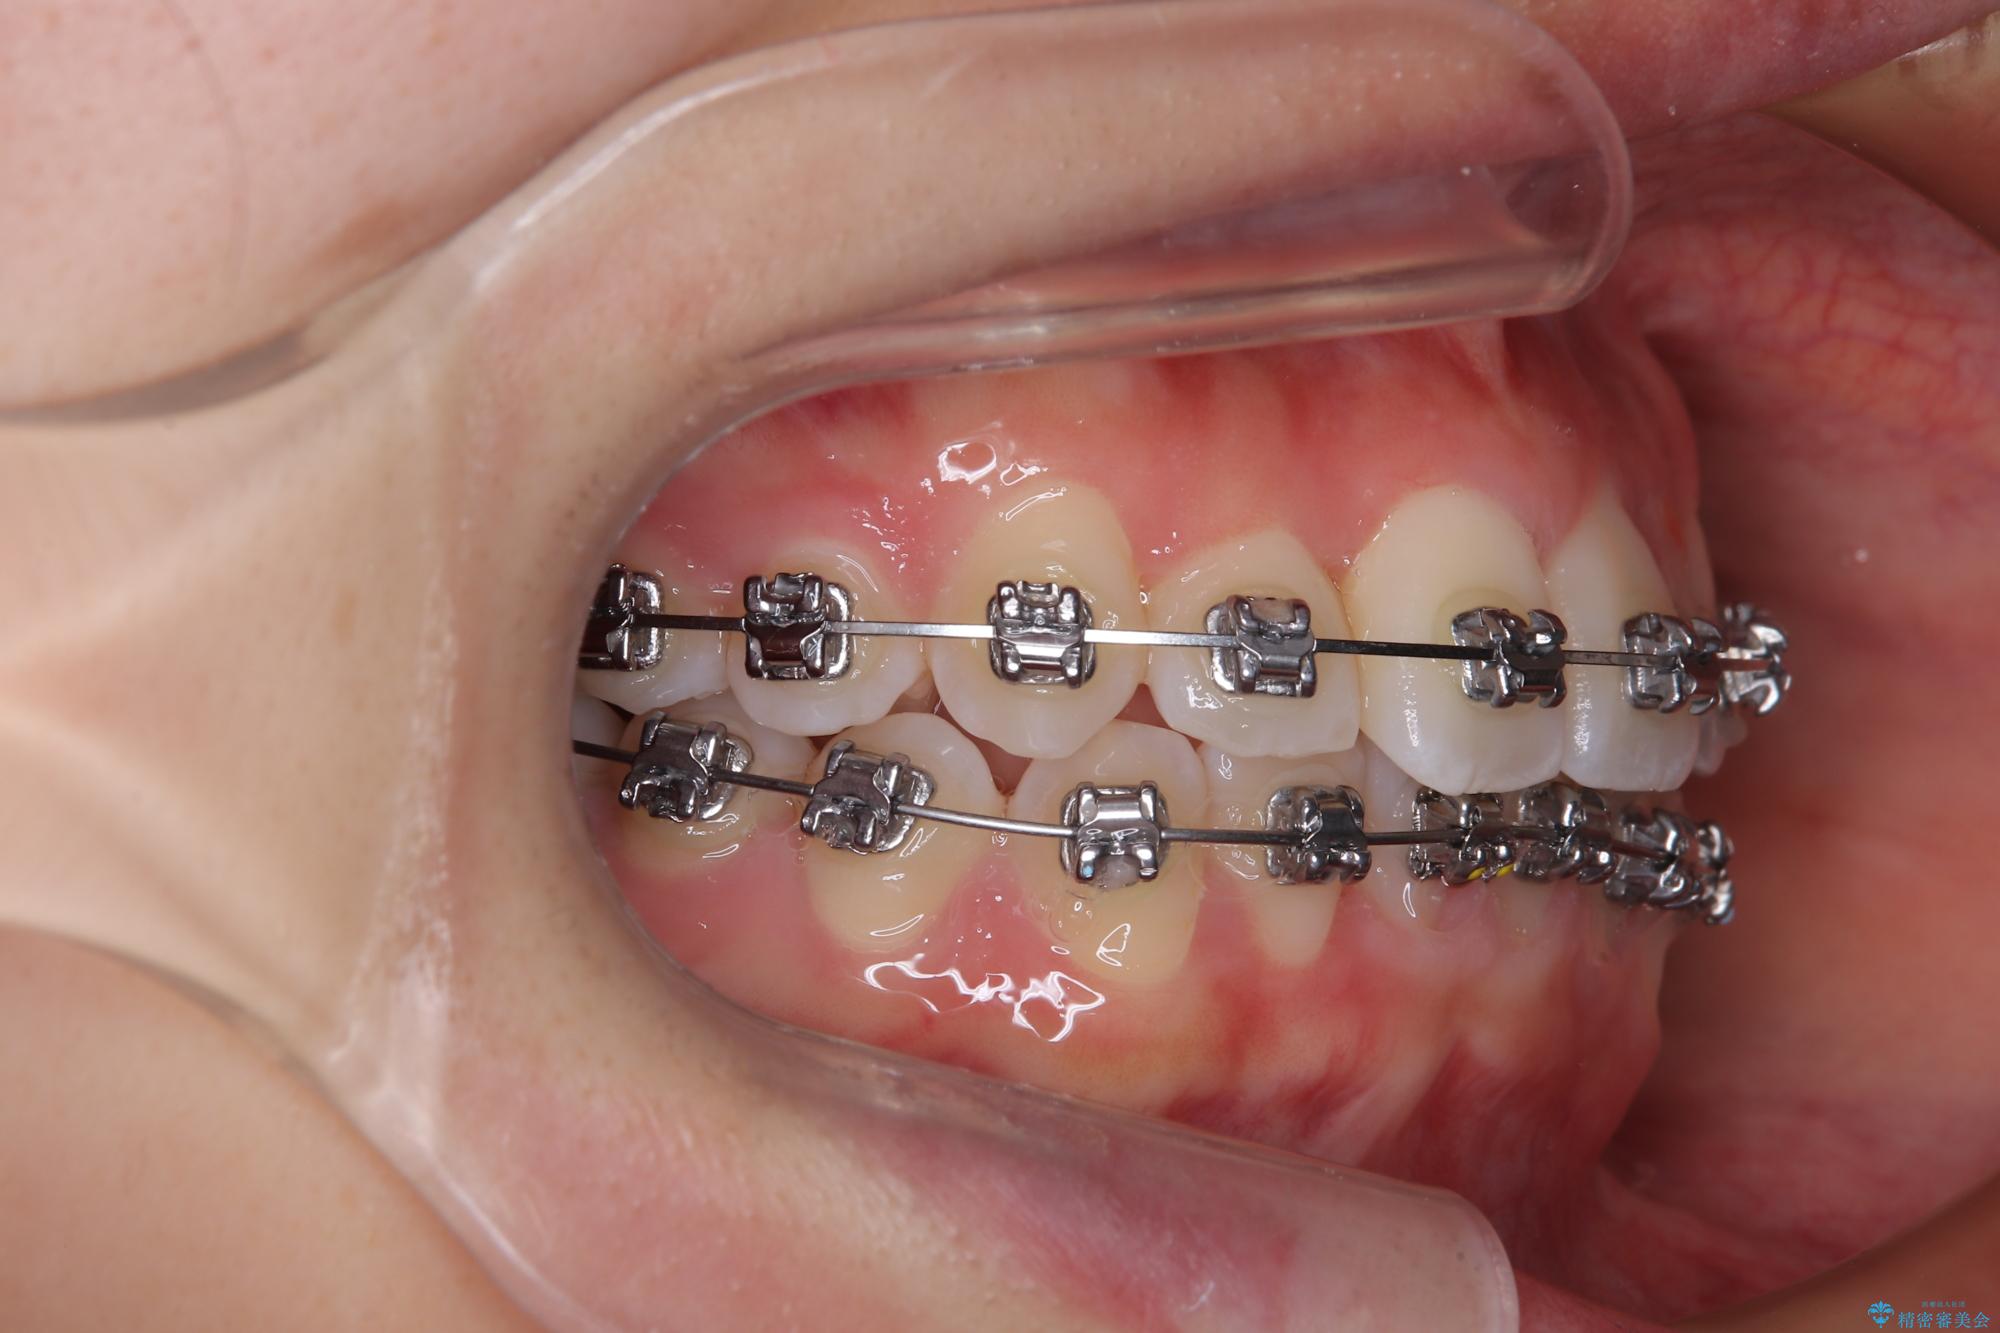

装置の外見を気にしていましたが、短期間で治療を終えることができるだろうと伝えると、安価であるメタルブラケットを選択されました。

想定通り、1年強で綺麗に仕上げることができました。